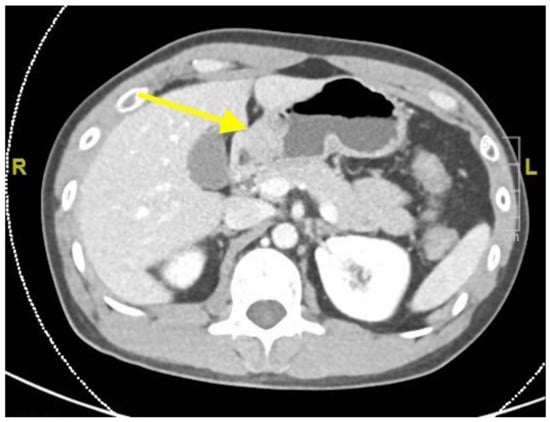

2. Case Report